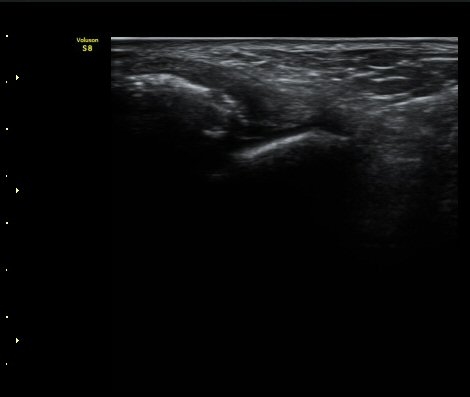

Àü°Å°ñºñ°ñÀδë Á¾´Ü¸é°Ë»ç»ó Àδë ÀδëÀÇ Àú¿¡ÄÚ ºÎÁ¾°ú ºñ°ñ

ºÎÂøºÎ ¹Ì¼¼ °ß¿­°ñÀýÀÌ °üÂûµÈ´Ù(±×¸² 3, 4).

ÃÊÀ½ÆÄÅõ½ÃÇÏ ºÎÇϰ˻翡¼­ ºñ°ñ°ú °ß¿­°ñÀý °ñÆí»çÀÌ¿Í ºñ°ñ°ú °Å°ñ »çÀ̰¡ ¹ú¾îÁø´Ù

(樨毢 1)